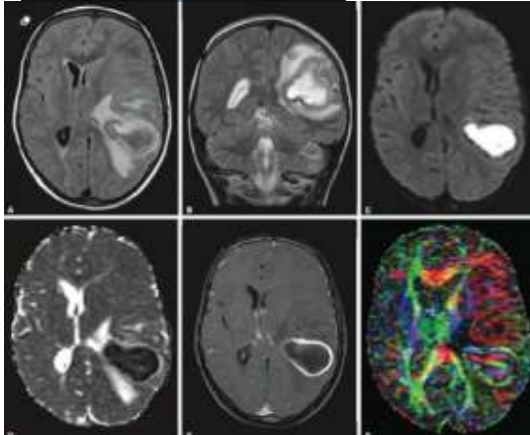

Paciente do sexo feminino, 30 anos, sem comorbidades, imunocompetente, apresentando histórico de cefaleia progressiva e hemiparesia direita. Encaminhada pelo médico assistente para realização de exame de imagem, que segue abaixo.

Baseado na imagem acima, assinale a alternativa correta.